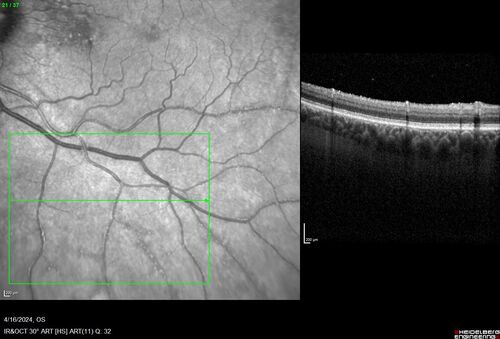

Posterior Pigment Dispersion Syndrome

81 year old man with cataract surgery 30 years ago and normal vision who had bilateral vitrectomy for dense floaters and has pigment on his IOL surface and all over the retina (but not on the cornea) VA 20/25 OU